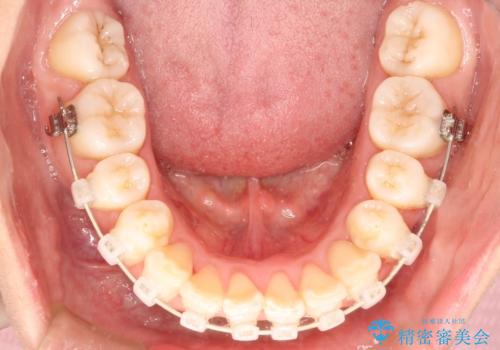

- 矯正装置

- 審美装置

- 治療期間

- 2年2ヶ月

- 治療回数

- 10-30回